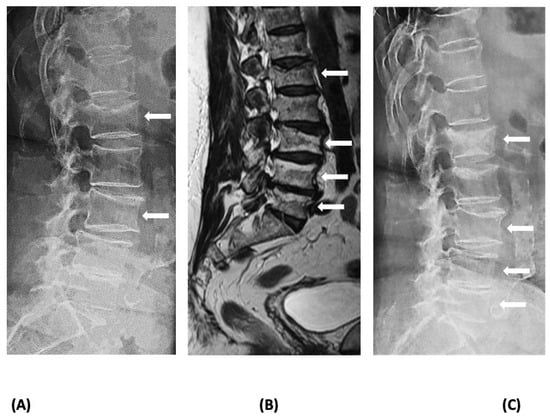

Vertebral compression fractures, which are the most common osteoporotic fractures, can cause significant back pain, limitation of activities, loss of independence, depression, chronic pain, and reduced quality of life, and increase the risk of imminent fractures and mortality [12,13]. While the most likely diagnosis in a patient presenting with a radiologically identifiable VFx 6 to 18 months after the last Dmab injection is RVFx, the recency of the fracture needs to be confirmed through an examination of earlier radiographs as back pain is a common symptom of elderly patients who may also have prevalent VFx [14,15,16]. If such radiographs are not available, recency can be verified using MRI, which can distinguish new from old VFx [17]. Severe back pain in a patient discontinuing or delaying Dmab treatment should always alert the physician of the possibility of RVFx, even if radiographs do not reveal spine deformities [17]. In such cases, described in the literature as acute non-collapsed VFx, a fracture may not be immediately identified but may be detected later in repeat radiographs; thus, MRI of the spine should be performed to confirm or exclude the diagnosis (Figure 2). In addition, other causes of VFx, e.g., malignancy, should be excluded. Establishing the diagnosis of RVFx may not be critical for the early management of patients, but it is essential for the longer-term therapeutic approach.

Figure 2.

Imaging of a patient with rebound-associated vertebral fractures 10 months after the last denosumab dose (4 months off treatment): (A) lateral lumbar spine X-ray at the time of acute back pain onset showing fractures at L1 and L3; (B) magnetic resonance imaging of the spine at the same time reveals additional recent fractures at L4 and L5; and (C) lateral lumbar spine X-ray 3 months later depicting deterioration of the deformities of the vertebrae (collapse of the acute, non-collapsed vertebral fractures). Fractures are indicated with white arrows.